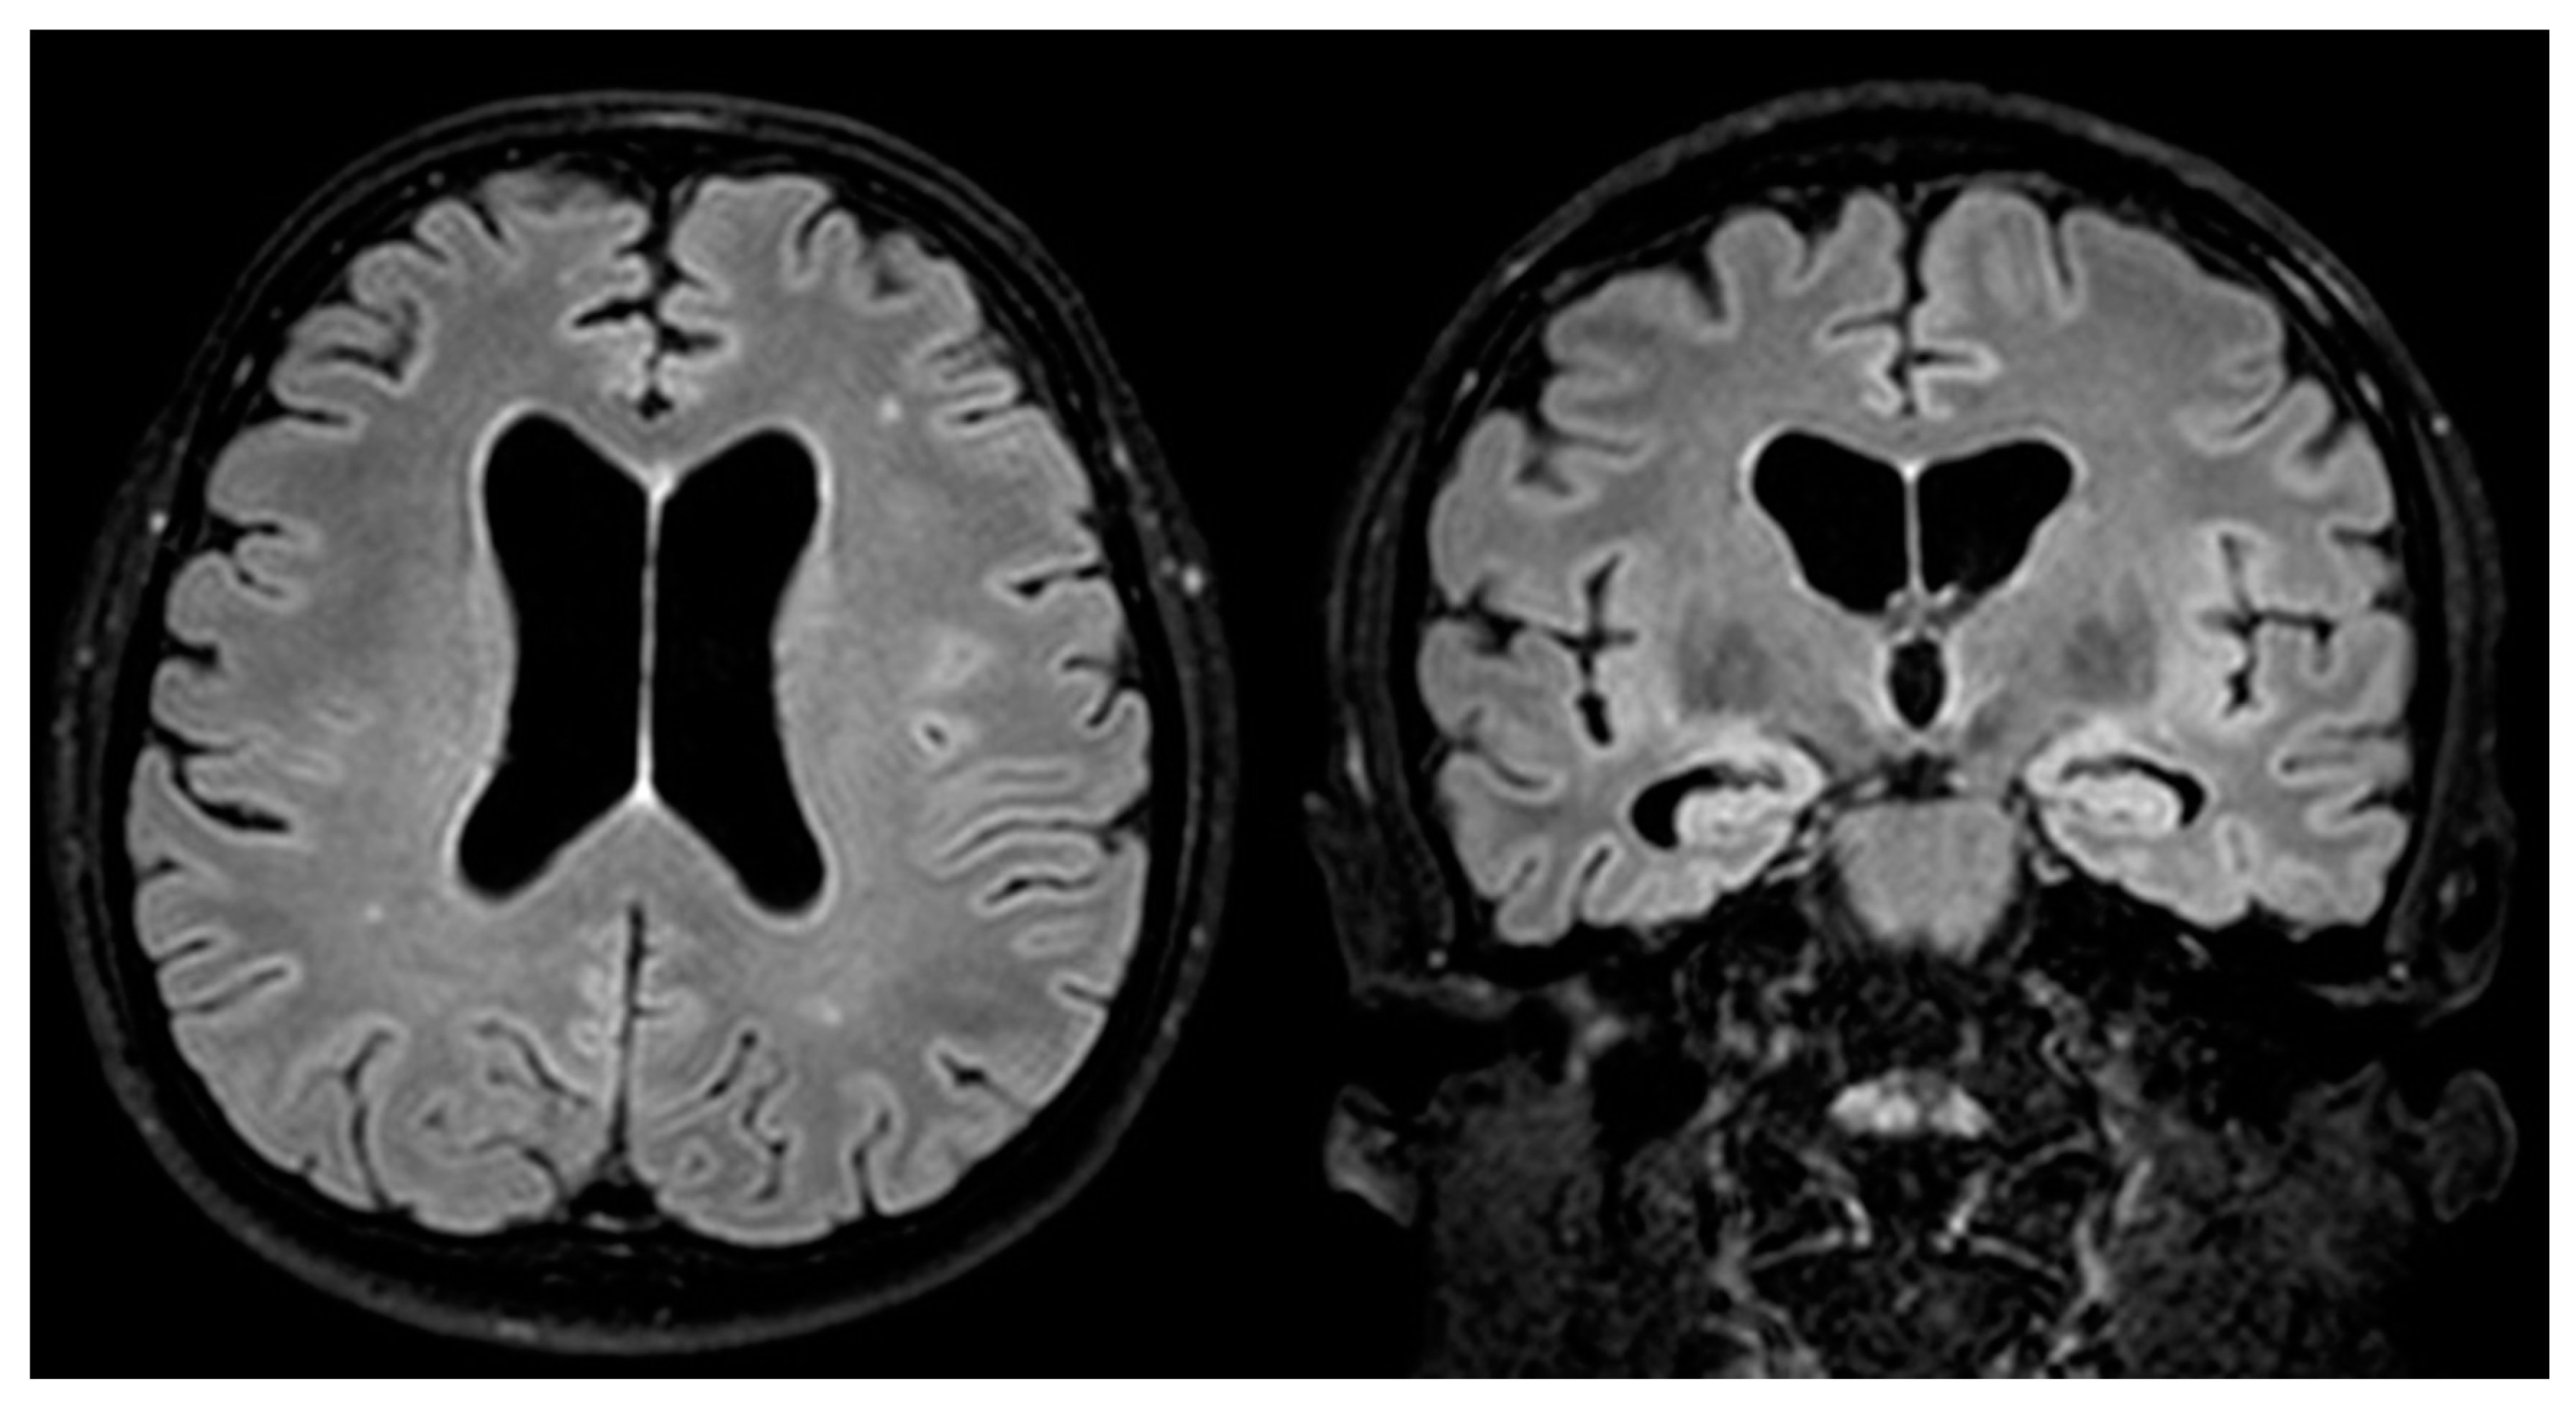

- Marano, E. Neurosyphilis with Complex Partial Status Epilepticus and Mesiotemporal MRI Abnormalities Mimicking Herpes Simplex Encephalitis. J. Neurol. Neurosurg. Psychiatry 2004, 75, 833. [Google Scholar] [CrossRef] [PubMed]

- Sesar, A.; Arias, M.; Requena, I.; Pereiro, I. Status Epilepticus Secondary to Luetic Encephalitis: Evolution of Neuroimaging Findings. J. Neurol. 2008, 255, 438–440. [Google Scholar] [CrossRef]

- Gaud, S.; Sauvée, M.; Muresan, M.; Gospodaru, N.; Foscolo, S.; Debouverie, M. Lésions Mésiotemporales Gauches et Amnésie Antérograde: Un Cas de Neurosyphilis. Rev. Neurol. 2011, 167, 833–836. [Google Scholar] [CrossRef] [PubMed]

- Derouich, I.; Messouak, O.; Belahsen, M.F. Syphilitic Limbic Encephalitis Revealed by Status Epilepticus. Case Rep. 2013, 2013, bcr2012008073. [Google Scholar] [CrossRef] [PubMed]

- Saunderson, R.B.; Chan, R.C. Mesiotemporal Changes on Magnetic Resonance Imaging in Neurosyphilis: Brief Communication. Intern. Med. J. 2012, 42, 1057–1063. [Google Scholar] [CrossRef]